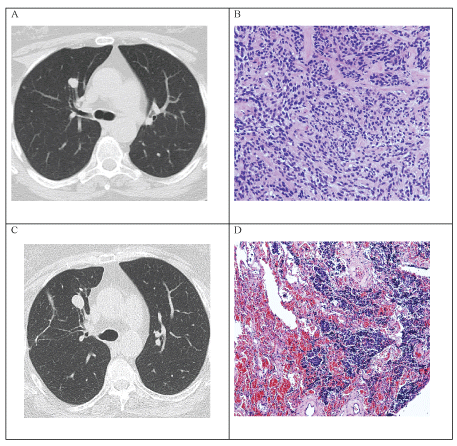

Figure 1: A) CT scan (from 2011) showing numerous small nodules bilaterally, one nodule 11 × 10 mm in size in the right upper lobe; B) Histopathology (from 2011) showing solid nests of slightly pleomorphic neuroendocrine cells; C) Follow-up CT scan (from 2016) showing growth of the nodule in anterior right upper lobe, now 15 × 13 mm in size; D) Histopathology (from 2016) showing diffuse proliferation of scattered neuroendocrine cells through alveolar parenchyma. View Figure 1

In 2011, a 69-year-old, non-smoker female presented with cough, wheezing and progressive dyspnoea. Lung function was normal (Table 1), chest CT was performed (Figure 1a and Table 1).

Surgical biopsy of the biggest nodule was performed. The pathomorphological changes as well as the immunophenotype were consistent with multiple neuroendocrine tumours and tumorlets (Table 1 and Figure 1b).

In 2016, five years after the presentation, the patient started to experience stronger episodes of dry cough, wheezing and dyspnoea. A CT scan demonstrated progression of the biggest nodule (Figure 1c and Table 1), which was negative on scintigraphy with octreotide (99mTc-HYNIC-octreotide SPECT/CT) suggesting absence of SSTR. The nodule was surgically removed (Table 1 and Figure 1d). The later testing for SSTR was negative, confirming the results of scintigraphy with octreotide.